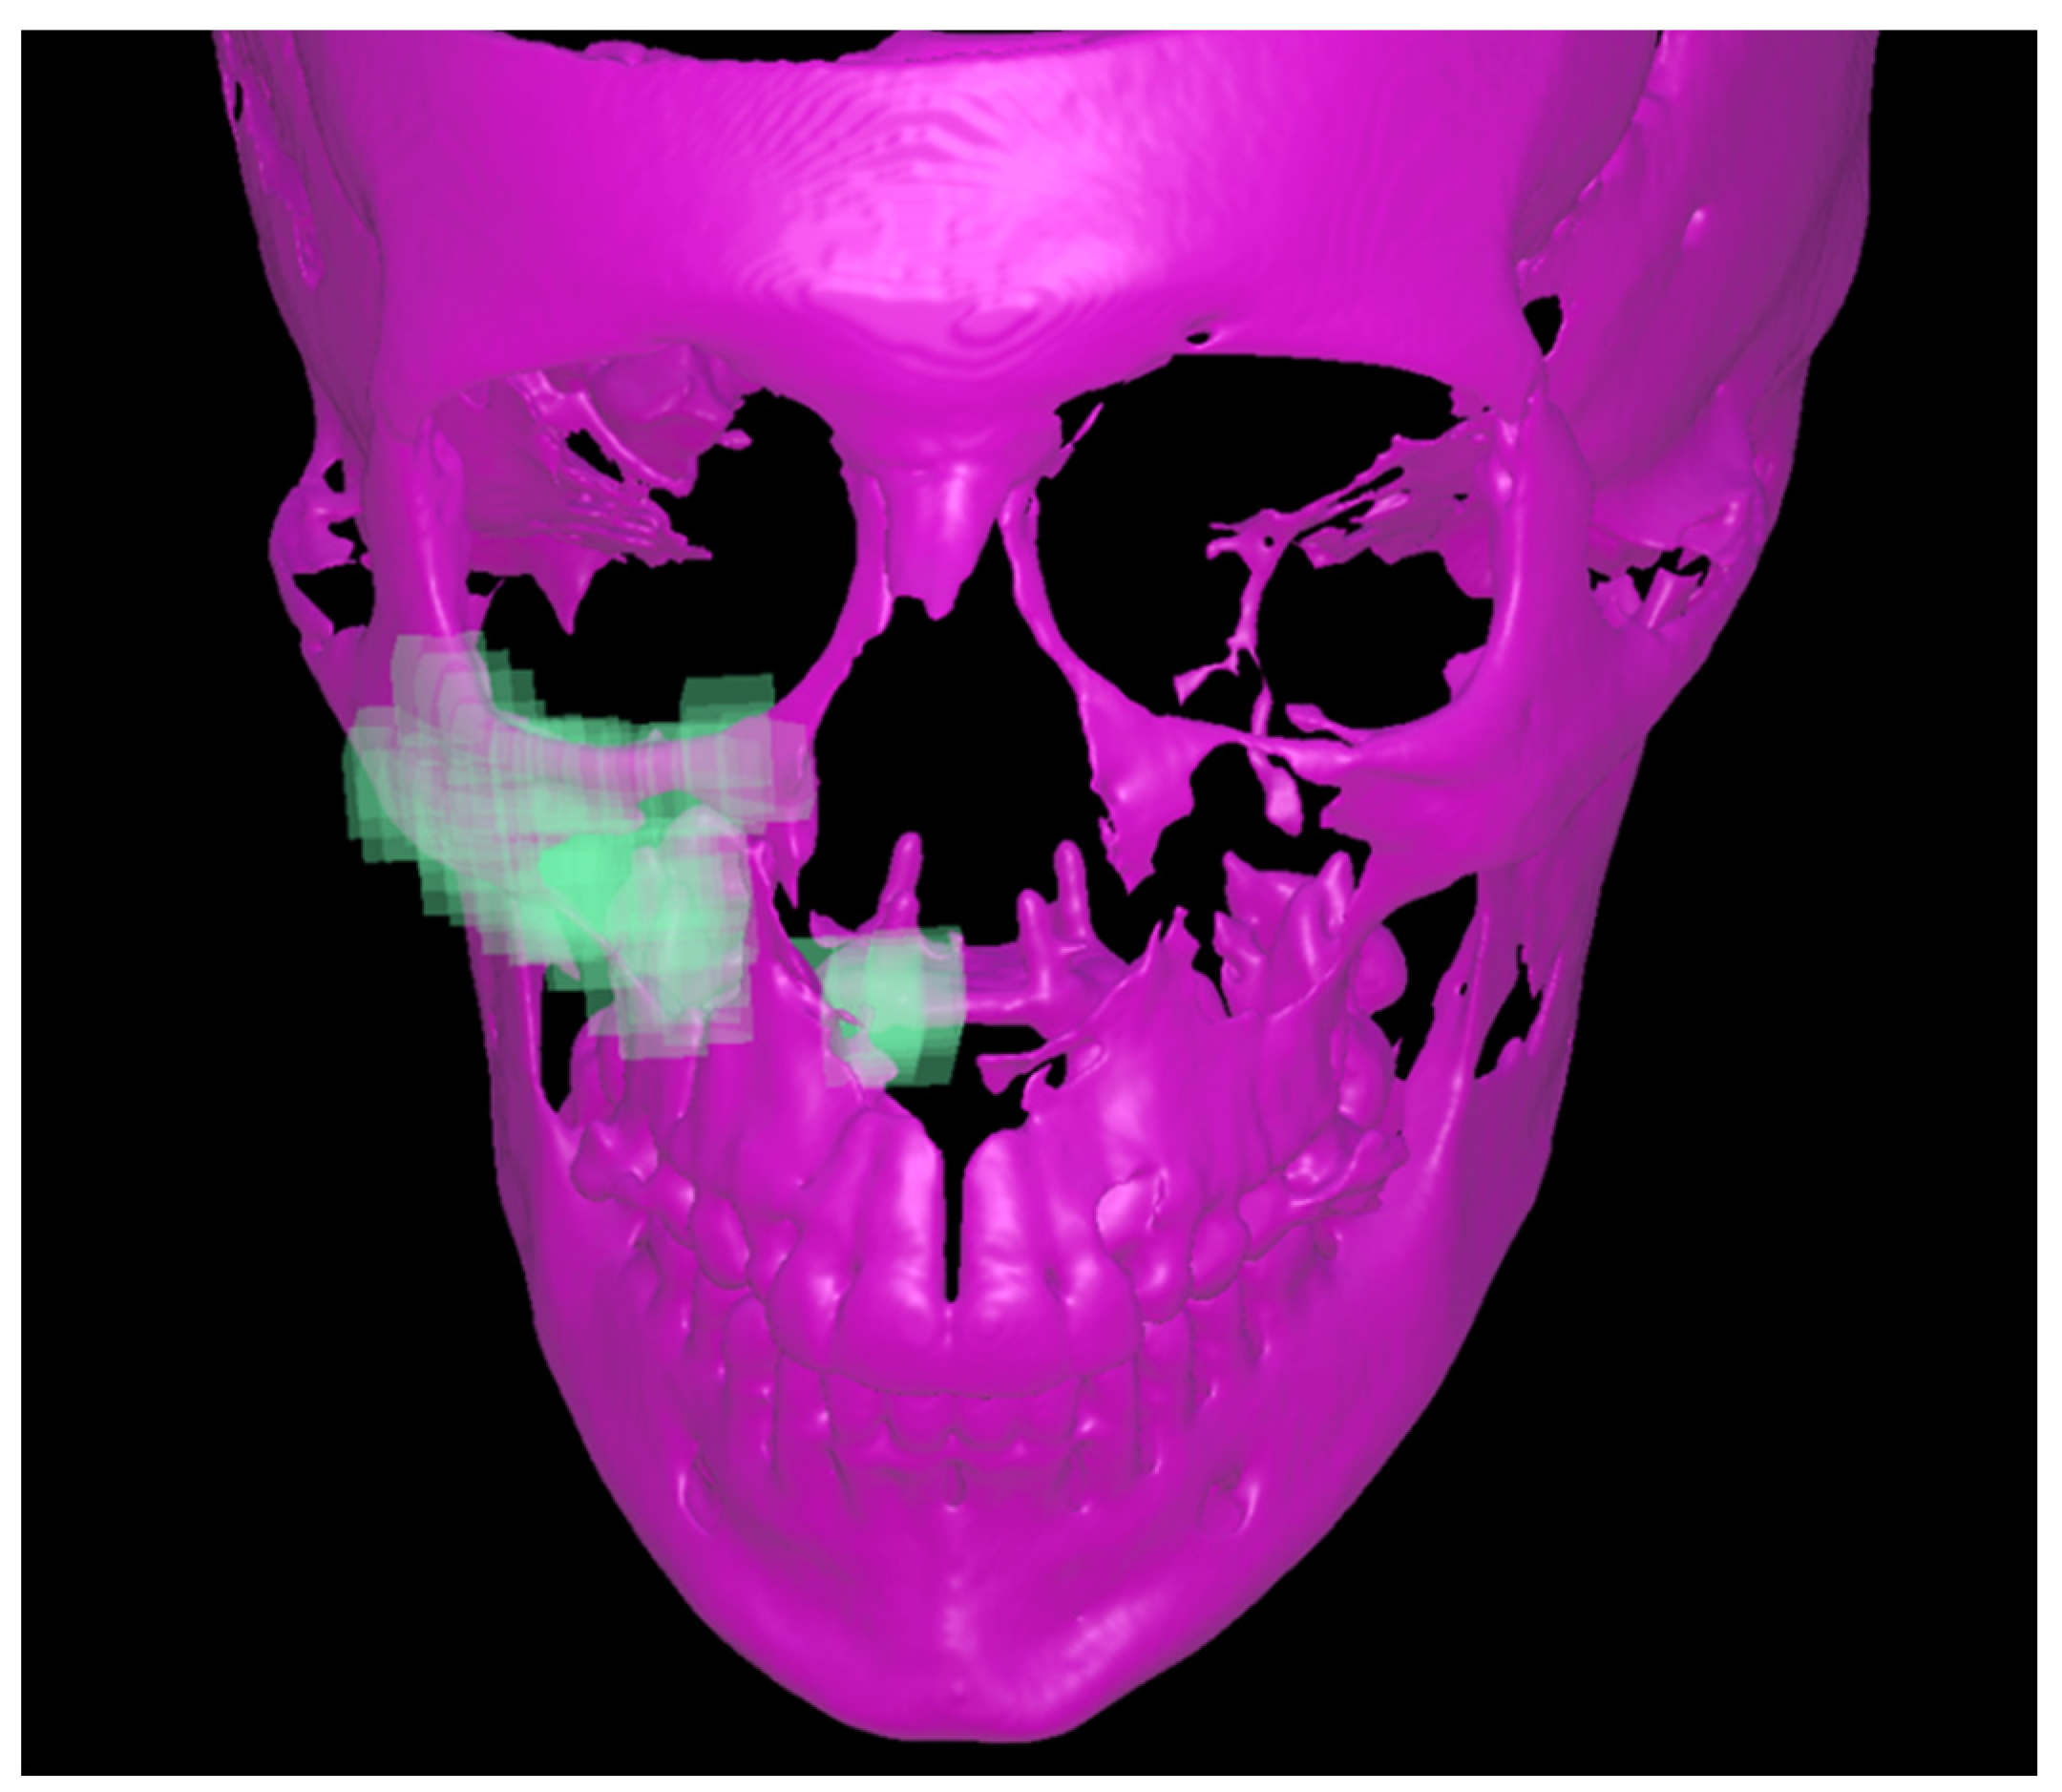

2.4. Three-Dimensional Visualization

3. Results